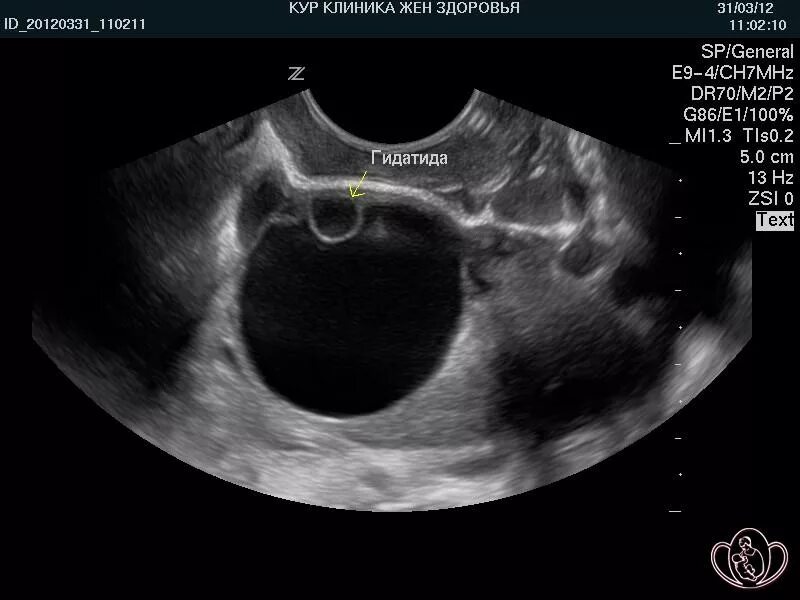

Фолликул 11 мм